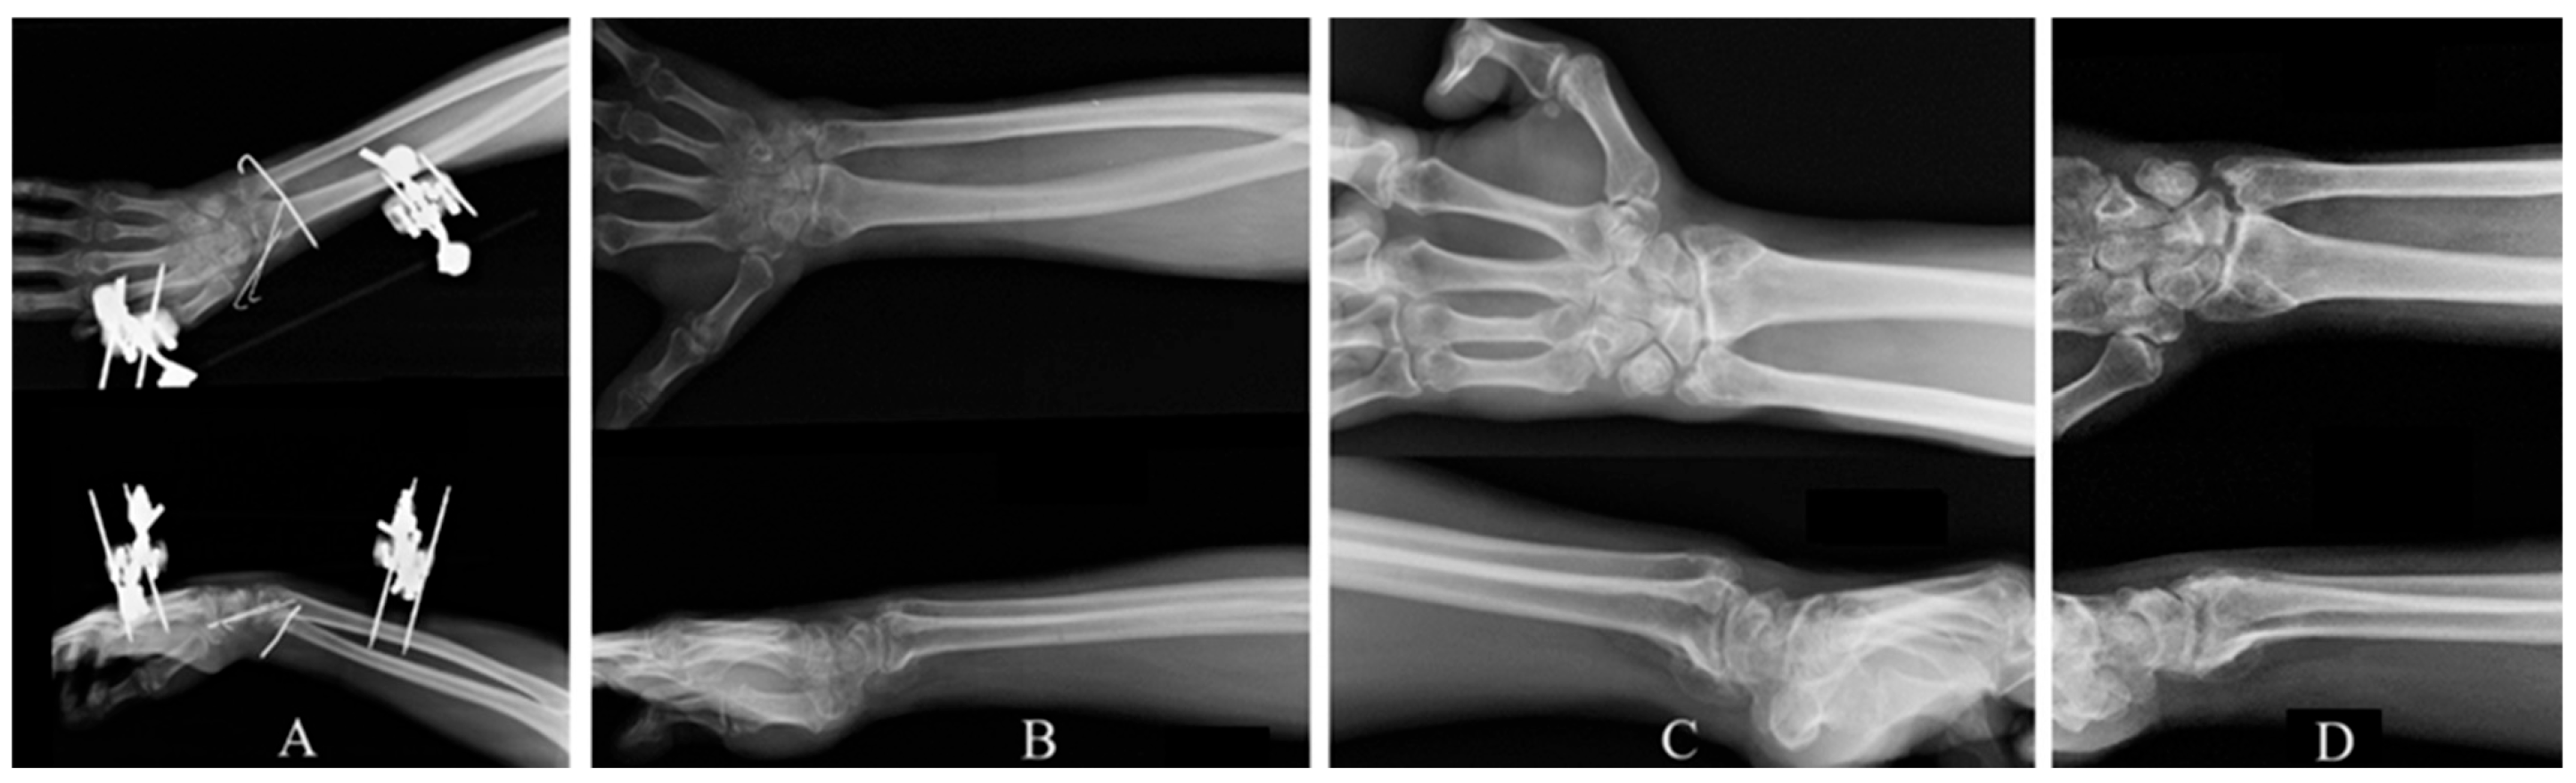

Open Radiocarpal Fracture Dislocation with Neurological Deficit Treated with Standalone External Fixation and Kirshner-Wires: Evaluation of Functional and Radiological Outcomes in a 4-Year Follow-Up: A Rare Case Report

Chaniotakis, C.; Koutserimpas, C.; Kapsetakis, P.; Tsioupros, A.; Alpantaki, K. Open Radiocarpal Fracture Dislocation with Neurological Deficit Treated with Standalone External Fixation and Kirshner-Wires: Evaluation of Functional and Radiological Outcomes in a 4-Year Follow-Up: A Rare Case Report. Reports 2026, 9, 57. https://doi.org/10.3390/reports9010057